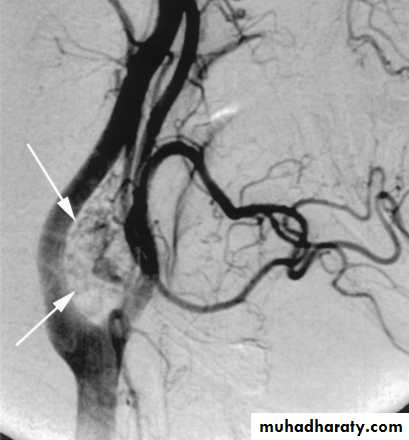

Carotid Body Tumor

Rare in childrenPulsatile, compressible mass

Mobile medial/lateral not superior/inferior

Clinical diagnosis, confirmed by angiogram or CT

Treatment

Irradiation or close observation in the elderly

Surgical resection for small tumors in young patients

Hypotensive anesthesia

Preoperative measurement of catecholamines

35

36